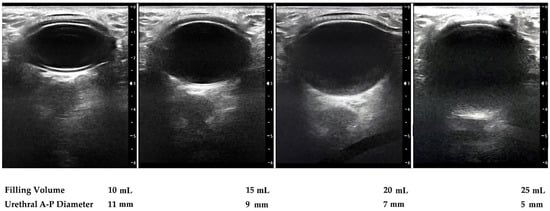

Perioperative intraurethral pressure measurement was carried out before and after ATOMS placement but before closing the incision, so that we could be sure the measurement was performed at the level at which the ATOMS device compresses the urethra (Figure 1). We measured this pressure by a T-DOC® air charged catheter inside the urethra at the point of contact between the ATOMS cushion and the urethra (Laborie, Mississaugua, ON, Canada), connected to Solar® urodynamic equipment (MMS, Enschede, the Netherlands). The system was calibrated before each measurement. The initial pressure was measured with an empty cushion, followed by 5 mL serial fillings until 30 mL was reached (Figure 2).

Figure 1. Operative view at the time of the ATOMS implant with a T-DOC air charged urethral catheter to perform intraoperative urodynamics. (a) Controlled system filling of the port through a perineal incision; (b) the ATOMS cushion inflated with variable volumes caused a change in intraurethral pressures that were registered by urodynamic equipment.